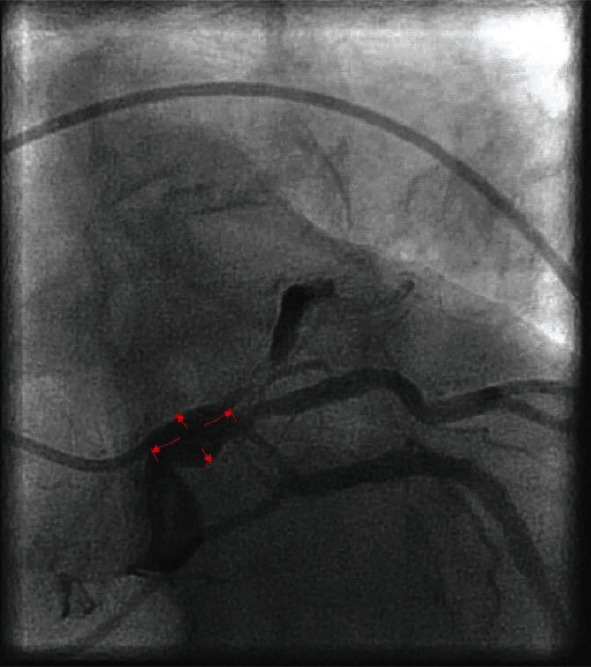

本病例是一名 59 岁的非裔美国女性,患有终末期肾病(ESRD),因胸部不适到急诊科就诊。她六个月前做过冠状动脉造影,结果显示心外膜冠状动脉没有闭塞性疾病。她的肌钙蛋白 I 水平升高,超声心动图显示新的区域室壁运动异常。她的 SARS-CoV-2 呈阳性。经过多学科团队会诊后,她接受了另一次冠状动脉造影检查,结果显示出现了新的严重多血管骨膜病变和左冠状动脉主动脉瘤。根据她的临床表现、血管造影结果和阴性的自身免疫检查结果,怀疑她患有与 COVID-19 相关的冠状动脉血管炎。该患者成功接受了冠状动脉旁路移植手术,术后恢复良好,未出现并发症。

We present the case of a 59-year-old African American female with end-stage renal disease (ESRD) who presented to the emergency department with chest discomfort. She had a coronary angiogram six months ago that showed no occlusive epicardial coronary artery disease. She had elevated troponin I levels and new regional wall motion abnormalities on echocardiogram. Her SARS-CoV-2 returned positive. After a multidisciplinary team approach, she underwent another coronary angiogram that showed new severe multivessel ostial lesions and a left main coronary artery aneurysm. COVID-19-related coronary artery vasculitis was suspected based on her clinical presentation, angiogram findings, and negative autoimmune workup. The patient underwent successful coronary artery bypass grafting and recovered without complications.